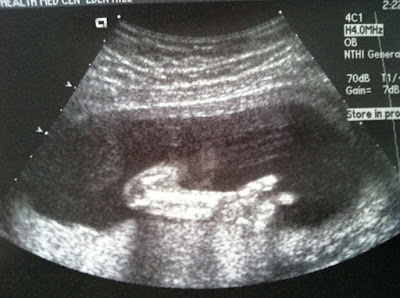

![]() |

| Her little arm and hand – she’s pointing! At least she wasn’t flipping us off, lol! |

Awesome pics of baby girl, looks like you will have a little acrobat on your hands with her already doing headstands lol. It also looks like she's giving you the peace sign. Your very lucky…

Cute photos! I love feets shots! At first I thought the last photo was her giving us the Peace sign.

Martine – Lol, you are the second person to tell me that it looks like she was flashing the peace sign. Very neat! And you're right, she was moving all over the place and trust me, my poor belly is feeling it! 🙂

Shirley – You're now the third person saying it looks like peace sign! My husband does this goofy thing about making finger guns (he's super cheesy), he even made me do it in one of our engagement pictures…and oddly enough the baby is doing it in one of her pictures. Crazy! She's probably going to be just like her dad. 🙂